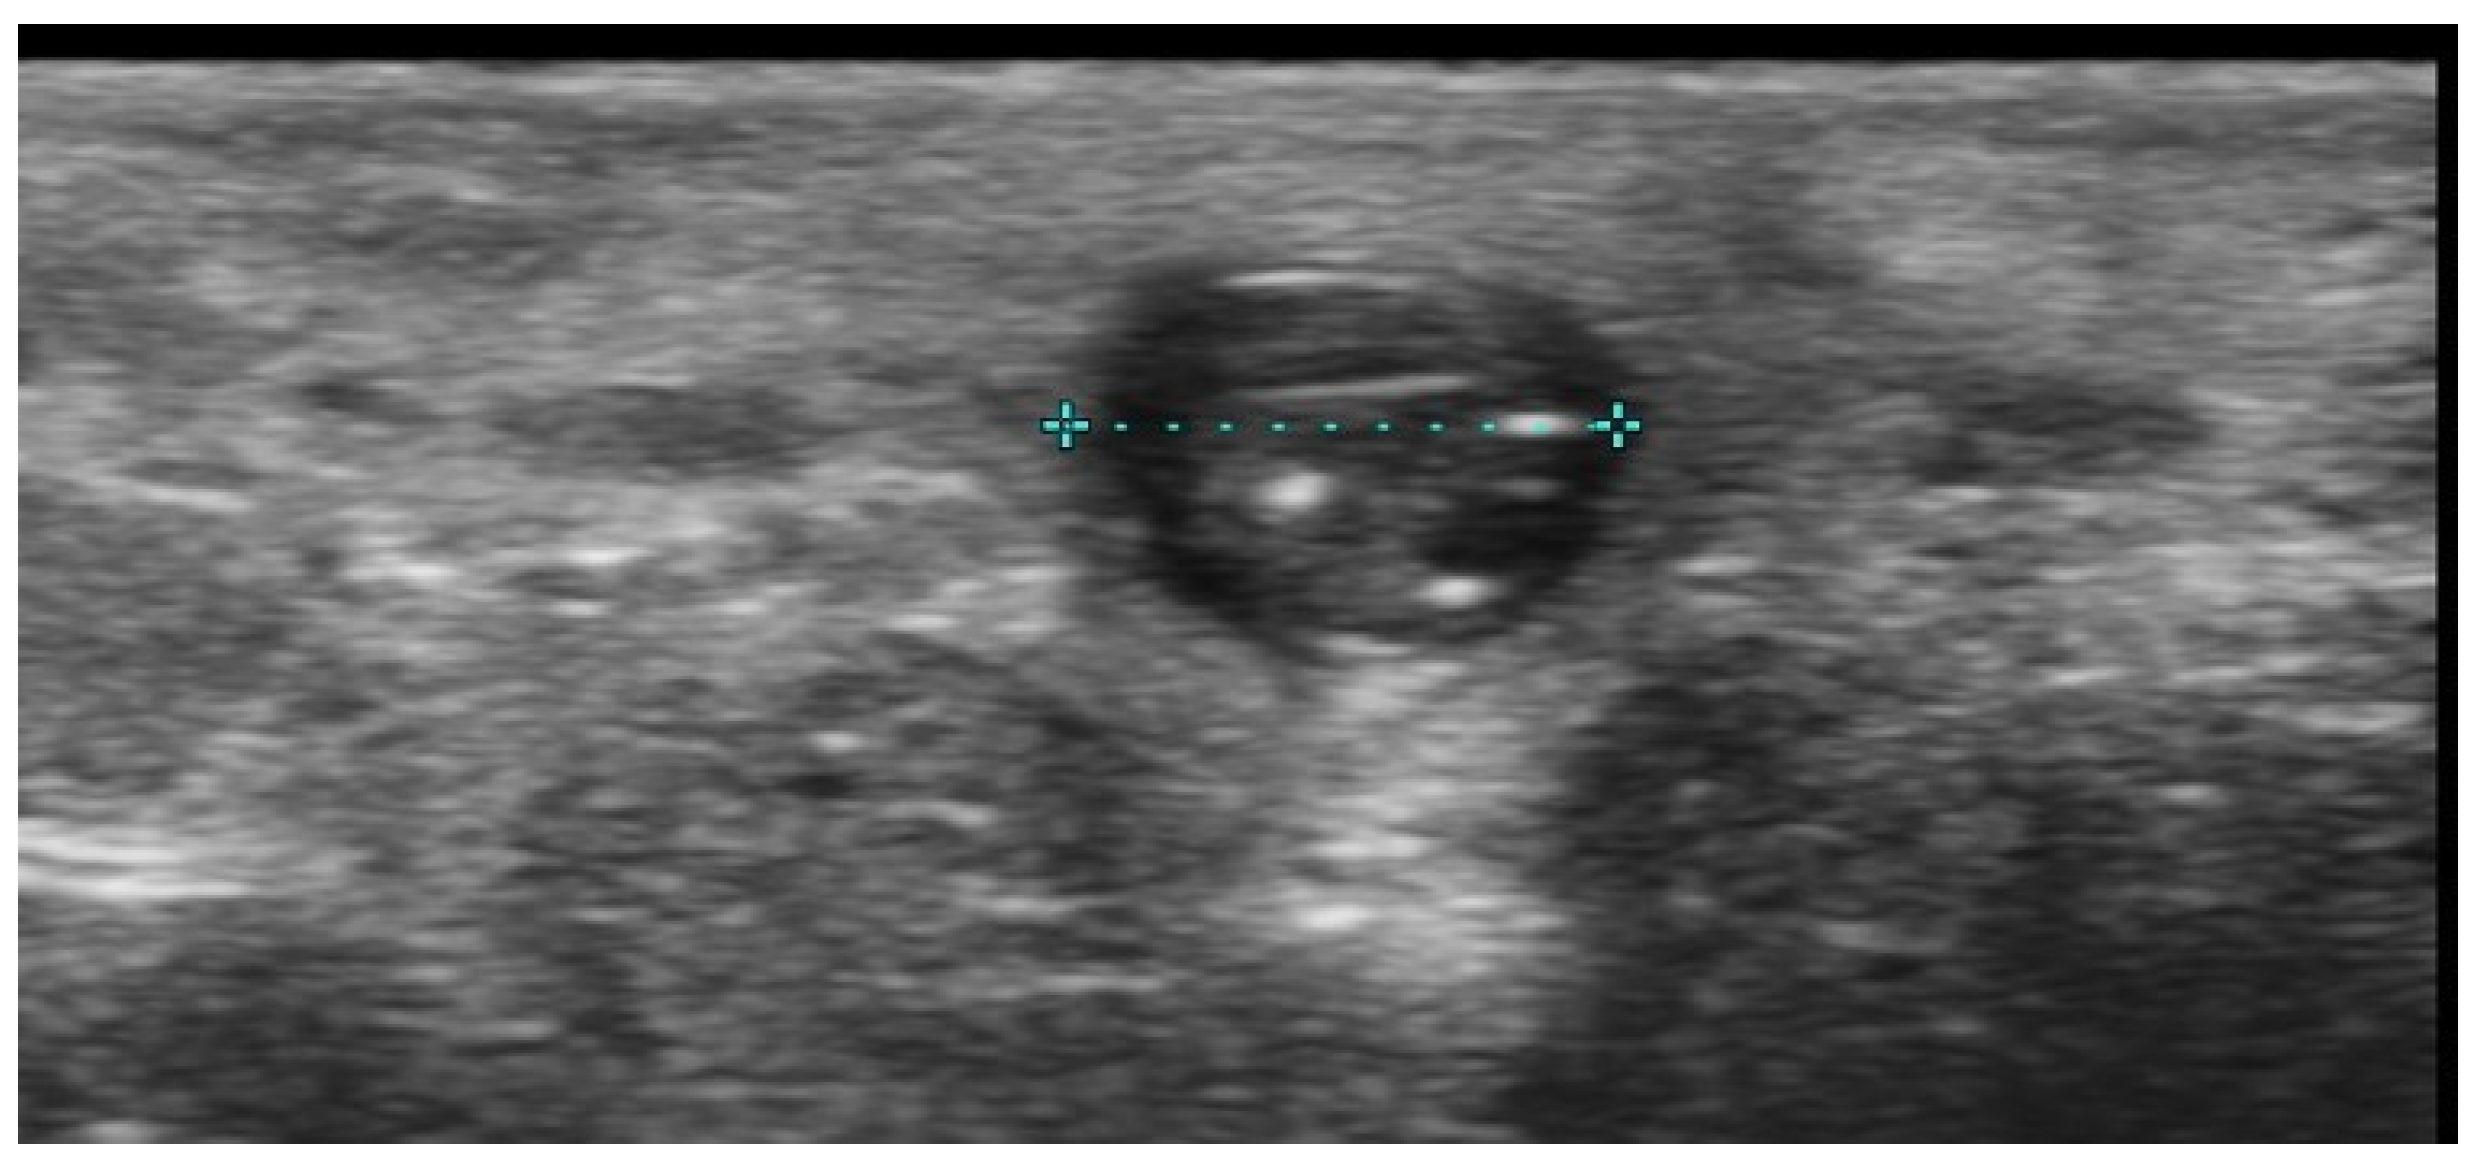

2. Infections